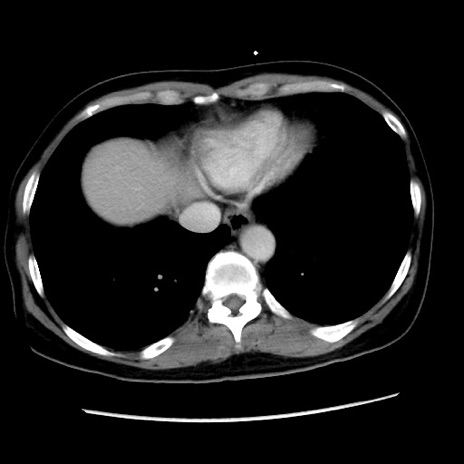

症例10(横断像)

【症例】 50歳代女性

【主訴】 腹痛

【現病歴】前日生レバーを食べた。今朝に排便あり。 昼前に突然発症の腹痛を生じ、当院救急外来を受診した。

【既往歴】 子宮筋腫にてで子宮全摘後

【身体所見】 意識清明、腹部:平坦、軟、下腹部やや左を中心に圧痛・反跳痛あり、筋性防御あり

【データ】WBC 7800、CRP 0.07